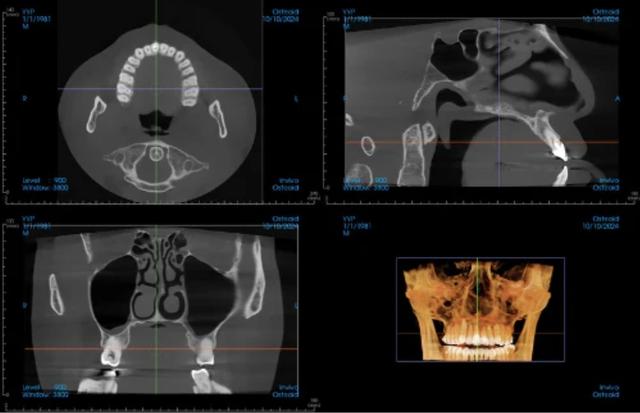

Our Ray Quantum CBCT system captures high-resolution 3D images of your jaw, teeth, bone structure, sinuses, and nerve pathways with exceptional clarity. Unlike traditional 2D X-rays that provide only a flat view, CBCT imaging reveals your complete dentofacial anatomy in three dimensions.

This technology enables Dr. Hoffman to diagnose with confidence and plan treatments that account for your unique anatomy, reducing surprises and improving long-term success rates.